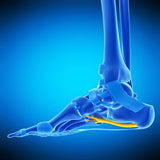

• Foot Anatomy & Pathologies

• Extensive Review of Plantar Fasciitis